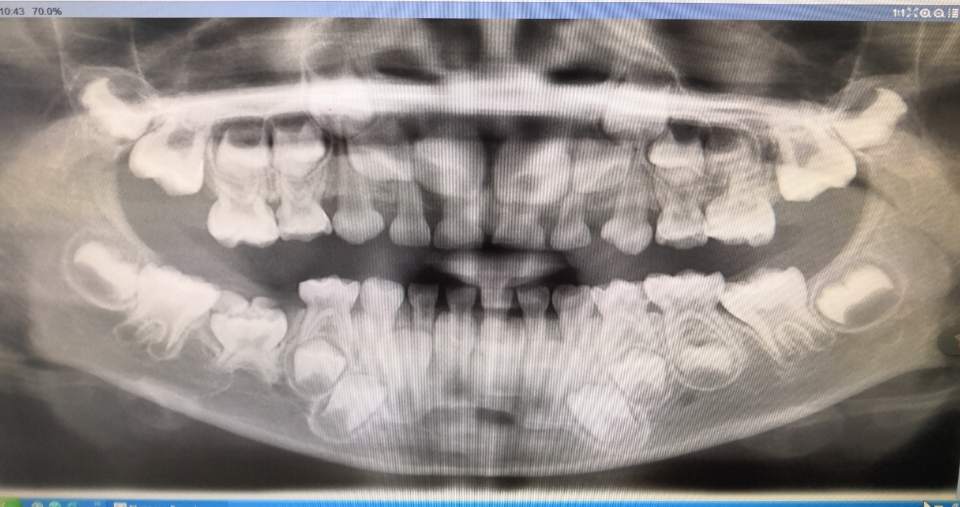

临床检查:患儿发育正常,上颌10颗乳牙正常萌出,下颌9颗乳牙正常萌出,右下第二乳磨牙未见萌出,对应区域牙龈没有隆起。全景片及牙片见下图。

X线片示:右下第二乳磨牙阻生,合面见两个高度钙化物影像,右下第二双尖牙缺失。

全景片示:右下第二乳磨牙阻生,合面钙化物影像

根尖片示:右下第二乳磨牙阻生,合面钙化物影像

手术取出的钙化物是三颗牙齿

处理:局部麻醉下,切开牙龈,翻瓣,取出钙化物,钙化物是三颗牙齿,见附图